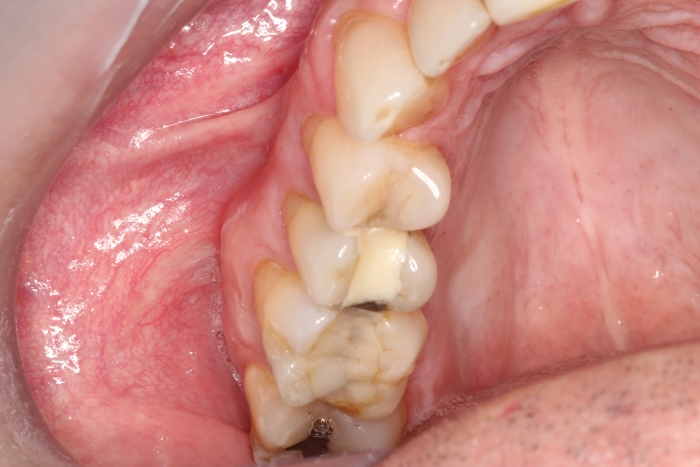

Extração - Implante imediato

Implante - Enxerto ósseo sintético